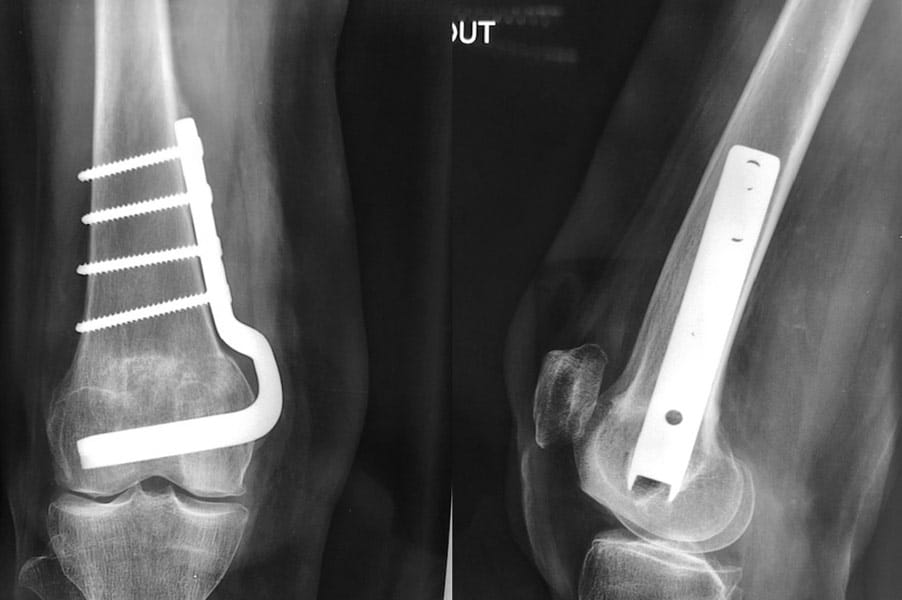

Déformation du genou en valgus (jambes en X), femme jeune (45 ans), ancienne handballeuse aux jeux de Séoul ; le fémur et le tibia sont déformés. Handicap majeur.

On réalise une double ostéotomie de varisation lors de la même opération, fémorale et tibiale, fixées avec des agrafes métalliques.